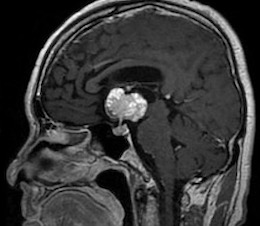

260331 60歳男性 頭蓋咽頭腫を開頭で摘出しました。